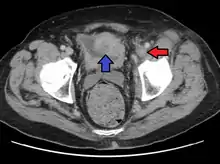

A person with a two hour history of phlegmasia cerulea dolens (left leg, right side of image) |